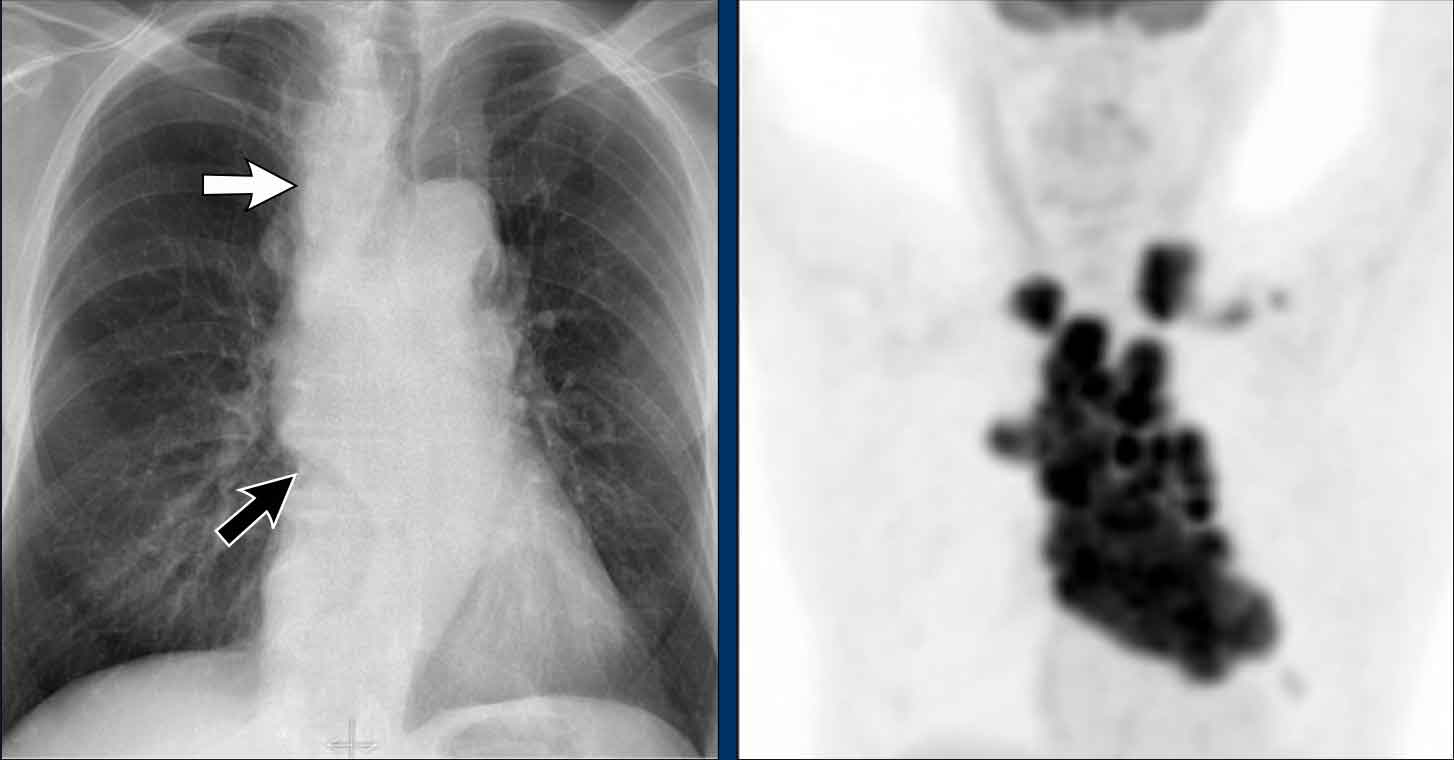

Displacement of the Azygoesophageal Line (2) – Subcarinal Lymphadenopathy

A common cause of displacement of the azygoesophageal line is subcarinal lymphadenopathy (station 7).

On the chest X-ray, note superior displacement of the azygoesophageal line just below the carina, consistent with enlarged subcarinal lymph nodes (black arrow).

Additional right paratracheal lymphadenopathy is seen, displacing the right paratracheal stripe (white arrow) and deviating the trachea to the left.

Continue with PET-CT...

PET Imaging

• PET-CT demonstrates extensive hypermetabolic lymphadenopathy in the mediastinum and neck, which is more conspicuous than on chest radiography.

• Cervical lymph nodes are involved—an important finding as they are accessible for biopsy.

Continue with images of CT and ultrasound...

CT Imaging

• Contrast-enhanced CT shows bulky subcarinal lymphadenopathy displacing the azygoesophageal recess and compressing the left atrium.

• Biopsy of a cervical node confirmed small cell lung carcinoma.